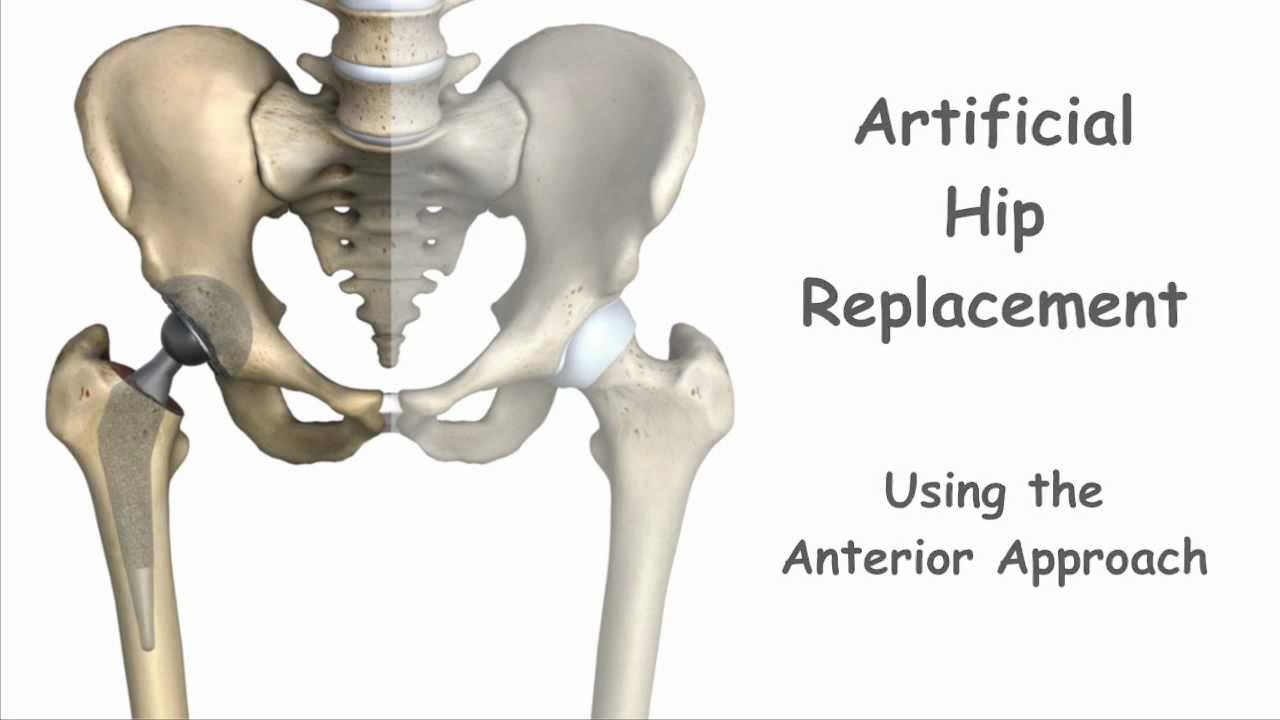

All About Anterior Hip Replacement

Hip Replacement Anterior Approach Protocol At Victoria Dearth Blog